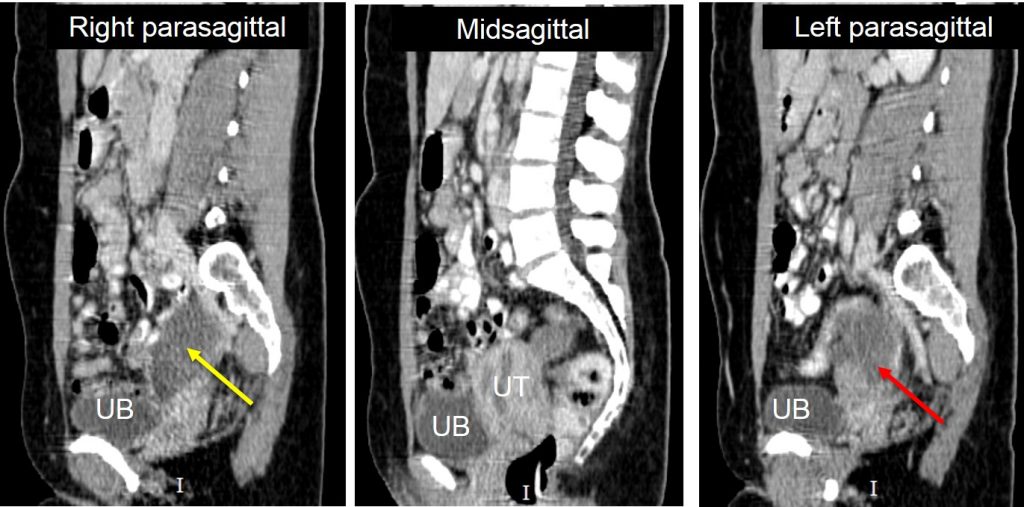

From radiologycases.my

Endometriotic cyst Radiology Cases Endometriotic Cyst Treatment endometriomas (ovarian endometriotic cysts) are a commonly diagnosed form of endometriosis, owing to the relative ease and. endometriomas are often densely adherent to surrounding structures, such as the peritoneum, fallopian tubes,. in the clinical management of endometriotic cyst, three. Your doctor will consider your age, any pain you’re in, and whether you plan to have a baby. Endometriotic Cyst Treatment.